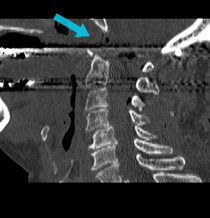

Post-surgical scan shows that bone has successfully been removed via EEA surgery to relieve pressure.

Doctors at UPMC performed surgery using EEA to remove the bone that was pressing on the patient's spinal cord, rather than traditional surgery through her mouth. Because the minimally invasive surgery was performed through her nose, the patient was able to start eating the day after surgery because her mouth was not affected. As with the traditional approach, she also needed to have rods and screws placed to prevent the pressure from coming back and to stabilize the upper spine and skull.